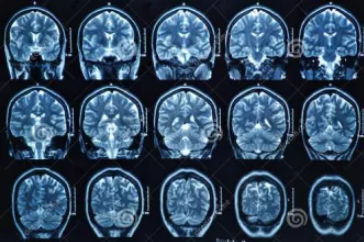

MRI檢查

MRI也就是磁共振成像,屬于斷層成像的一種,它是利用磁共振現象從人體中獲得電磁信號,并重建出人體信息。通過檢查可獲得橫斷面、矢狀面、冠狀面的影像,空間分辨率高,是神經系統、脊柱脊椎部分檢測的第一選擇。

無論是DR還是CT,由于對部分軟組織的分辨率不足,所以軟組織疾病的排查便成了它們的短板,而磁共振的長處恰恰就是清晰顯示軟組織疾病,對于膀胱、直腸、子宮及關節肌肉的檢查優于CT。MRI適用于神經系統病變、心血管系統、胸部病變、全身軟組織病變等。